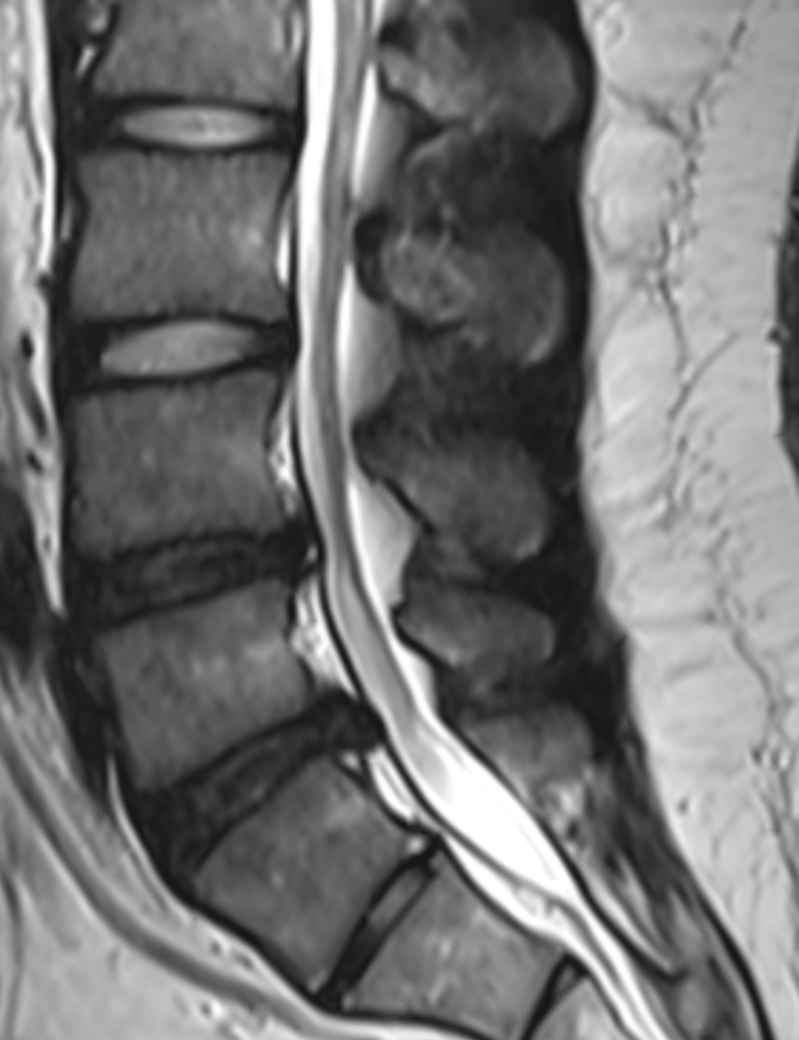

이정도면 경미한 허리디스크인가요??

2년전 찍은 mri인데 이때보다 통증이 더 심해져서요 ㅠㅠㅠ

mri 상으로 이정도 허리디스크는 돌출?정도이고 초기 수준인가요??..